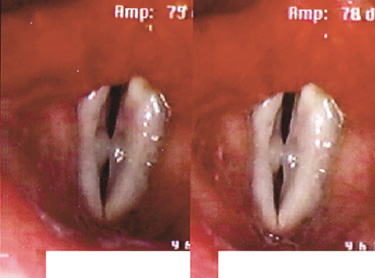

성대낭종은 과도한 음성사용으로 인해 주머니 형태의 양성종양이

점막아래에 형성된 것으로 성대점막의 면을 따라 둥근 공 모양으로 나타나는

표피양낭종과 점액을 분비하는 점액선의 관이 막혀서 생기는

저류낭종으로 분류할 수 있습니다.

표피양낭종은 성대에서의 돌출이 미미하고

저류낭종은 성대점막직하방에서 발생하여

후두 내부로 돌출하는 양상을 띠게 됩니다.

성대낭종은 성대결절이나 성대폴립과 감별 진단하는 것이 중요합니다.